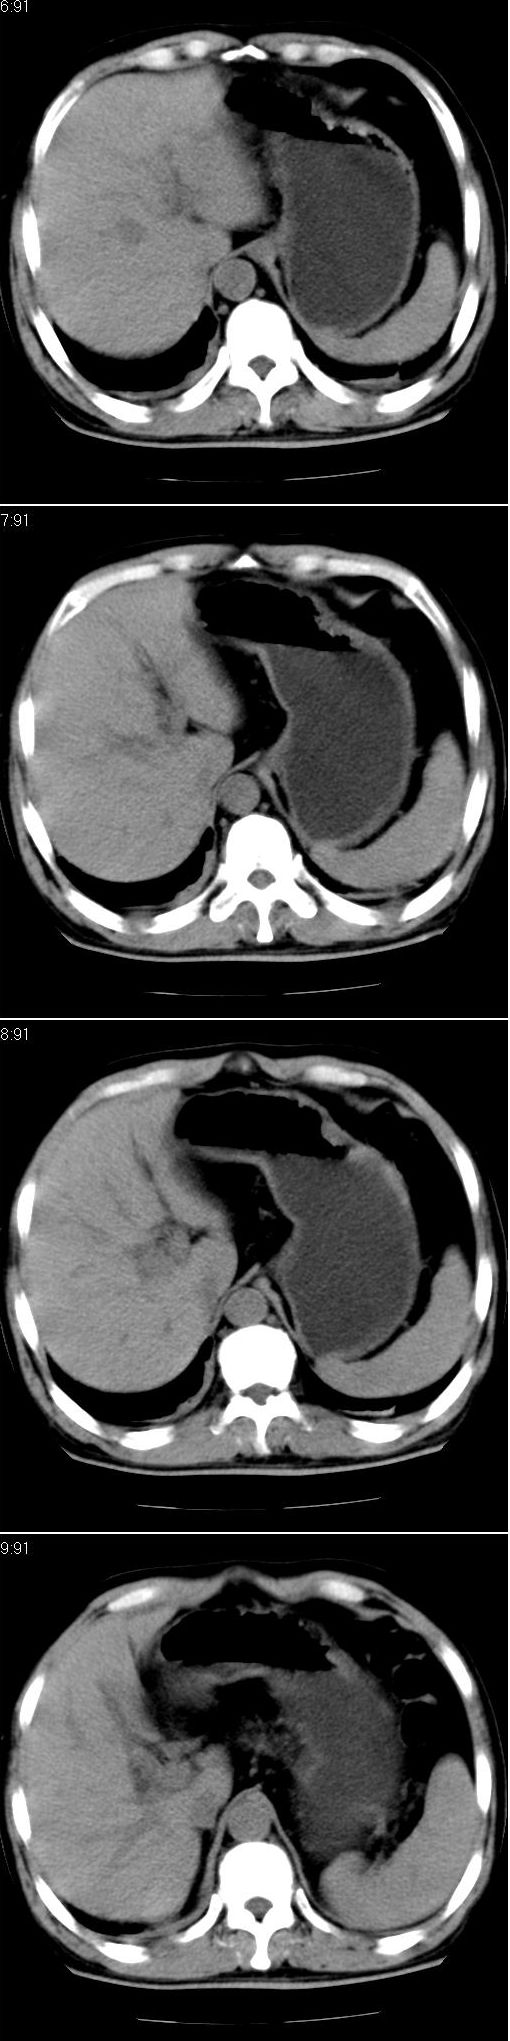

男,57岁。因胆结石阻塞性黄疸入院。这是胆囊切除术后的照片,看看此片到底有什么问题。

胆总管有没有问题,尤其是肝门附近的胆总管?

肝门附近的胆总管轻度扩张 请楼主复习术前片

肝内外胆管轻度扩张,胆囊窝内见引流管考虑胆囊切除术后改变.胃窦部软组织似增厚,建议胃镜检查.

在手术切除胆囊的过程中,发现肝门部胆总管恶性占位,因为家属不同意手术,没有切除,能看出来么?

不是楼主提醒还真看不出来,肝内胆管扩张。略显僵硬。

肝内外胆管轻度扩张。楼主提示左右肝管合汇区域壁稍厚。胆总管末段壁似也稍厚有轻度强化。就现有资料诊断难。